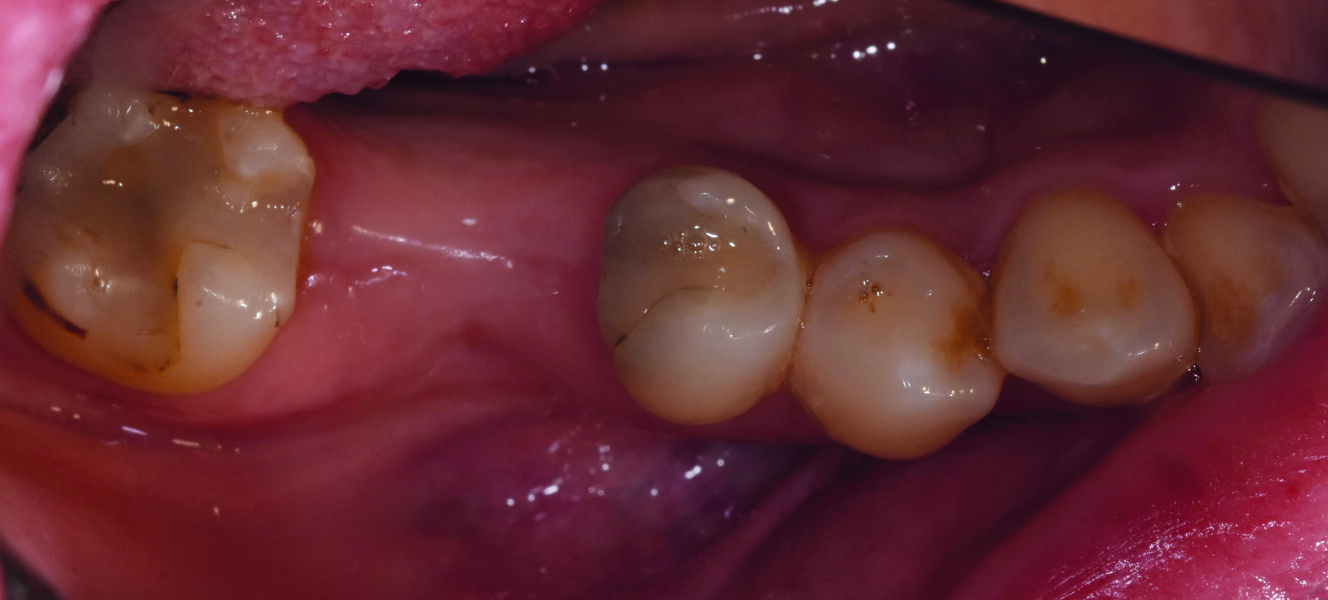

Trois mois plus tard. Second temps du protocole en deux temps. Légère incision crestale, dépose de la vis de couverture et ensuite mise en place de la vis de cicatrisation (Fig. 14).

Fig. 14 : Vue occlusale du pilier de cicatrisation vissé dans le col implantaire.